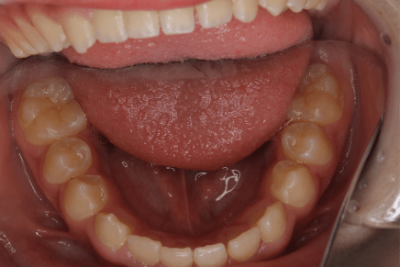

写真④:使用する装置例

使用する装置例

写真⑤:使用する装置例